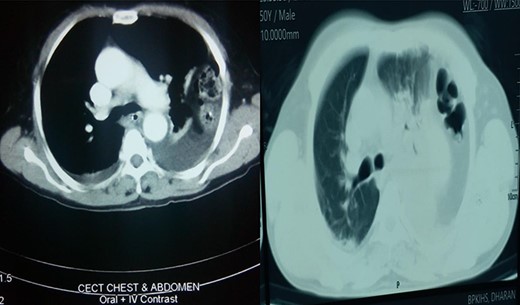

A retrospective analysis was carried out to review records of patients who presented to our department over a period of 3 years from December 2017 to January 2020. All patients with diaphragmatic hernias were included in the study. Preoperative diagnosis of diaphragmatic hernia was based on history, clinical examination and radiological investigations (chest X-ray and CT) (Figs 1 and 2).

Axial section showing collapsed left lung with bowel in left thoracic cavity.